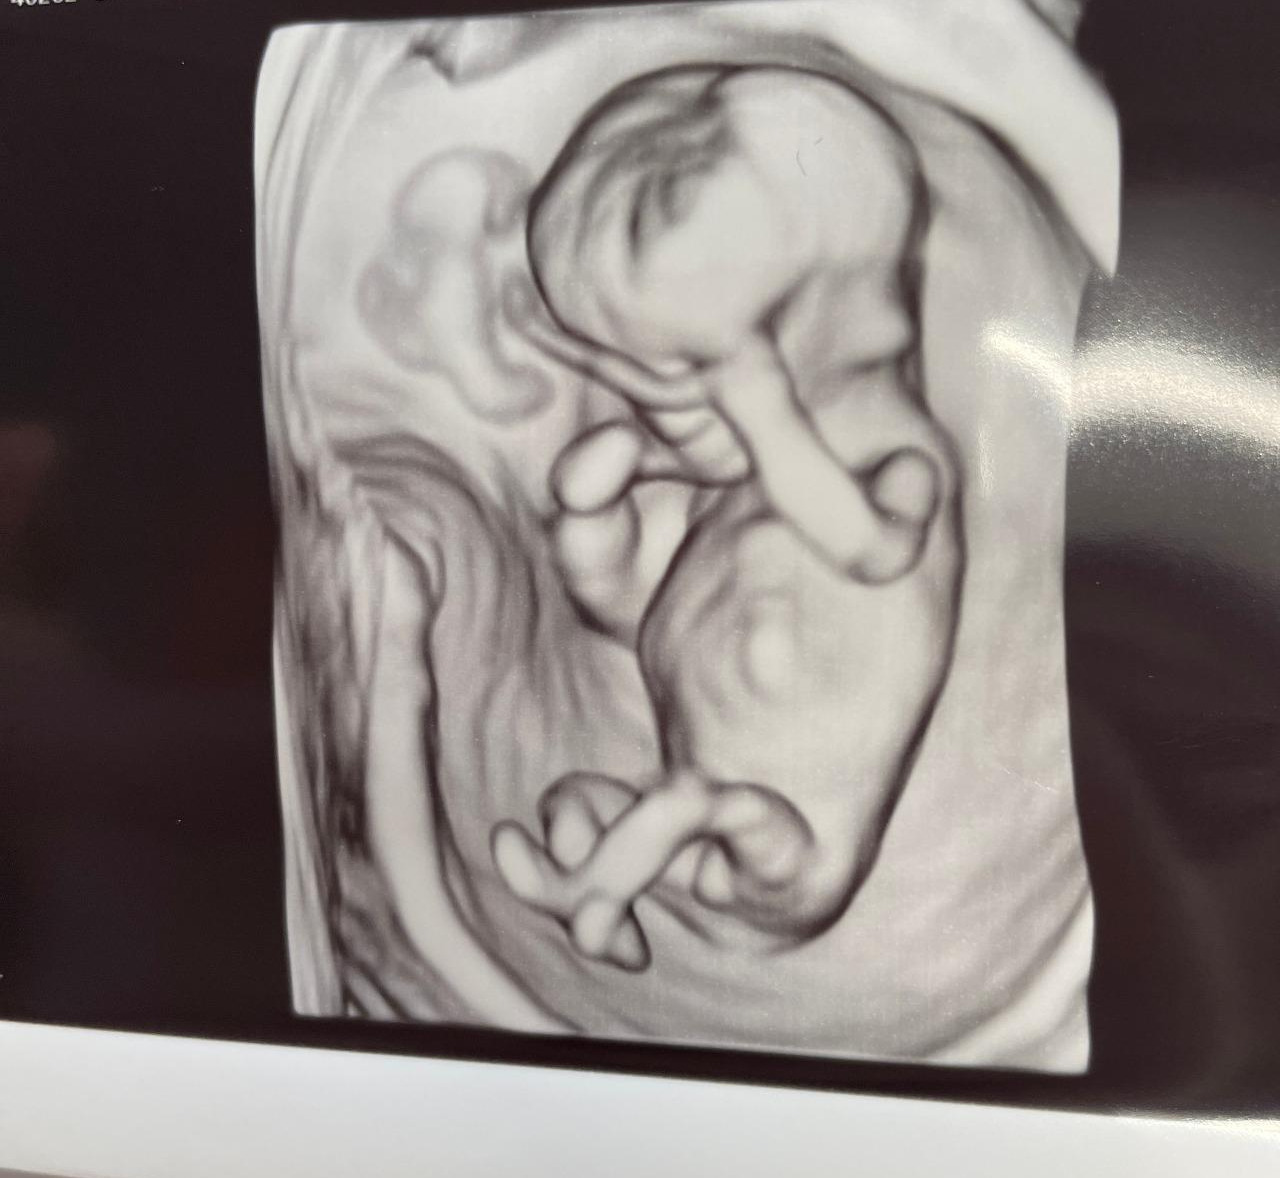

성별을 알 수 있는 초음파 검사날.

뱃속 아기는 웅크리고 낮잠을 잤다. 두 손으로 눈을 가리고 두 다리를 꼬고 자는 듯한 모양이 꽤 귀여웠다.

요리조리 각도를 재던 선생님은 초음파 기계로 배를 흔들어 아기를 깨우려 했고, 심지어는 내게 잠시 옆으로 누워 벨리댄스를 추듯 골반을 흔들어보라고 했다.

잠을 푹 자는 녀석을 보며 태어나면 '잠을 잘 재울 수 있겠구나' 싶은 희망적인(?) 수면교육의 기대감을 걸며, 나는 옆으로 누워 벨리댄스를 추듯 골반을 흔들었다.

그 틈에 깬 녀석의 다리 사이를 드디어 염탐할 수 있었다. 결과는 역시나... 아들이었다.

다리 꼬고 누운 녀석의 다리 사이... 뚜렷한 아들의 증거.!!!